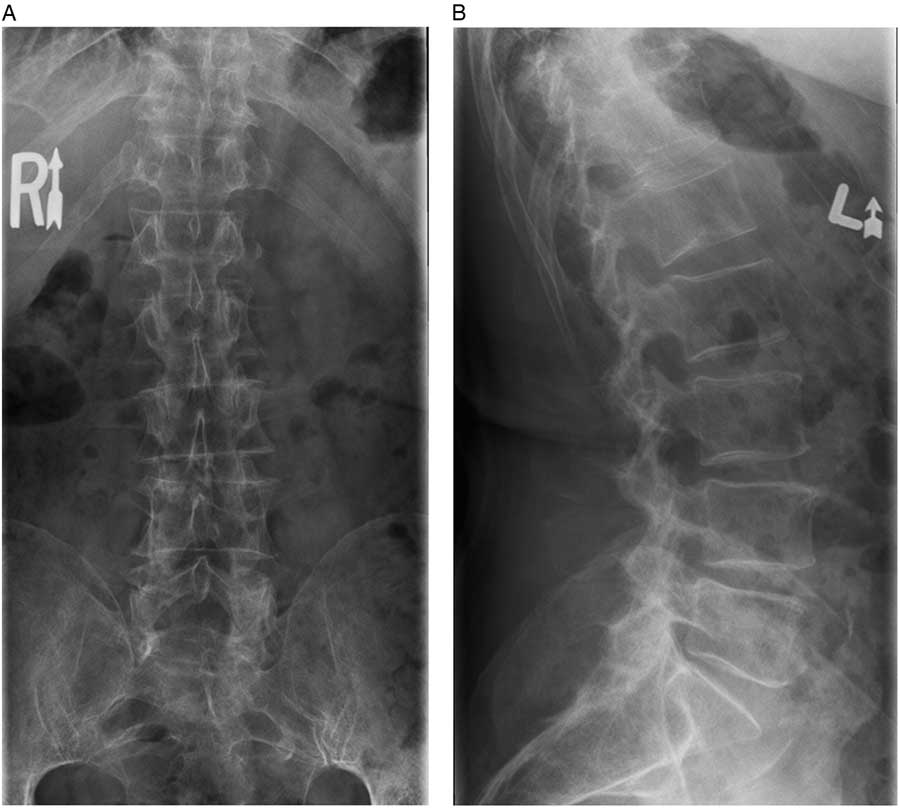

The family physician ordered thoracolumbar spine radiographs, which subsequently were reported as being free of any lesion or fracture (Figure 1). His past medical history was remarkable for a transient ischemic attack and hypothyroidism for which the patient was taking clopidogrel bisulfate, 75 mg once daily, and levothyroxine, 100 μg once daily, respectively. The patient’s routine laboratory investigations over the previous year demonstrated normal vitamin D, sodium, potassium, and chloride levels as well as a normal urinalysis. Two years prior, the patient did have a transient pancytopenia, which, after resolving spontaneously, was not investigated further. It was recommended by the family physician that the patient try conservative measures for his lower back pain, including the use of nonsteroidal anti-inflammatory medication.

Figure 1 A) Anterior-posterior and B) lateral radiographs of the thoracolumbar spine acquired in the community. No spinal injuries were noted.